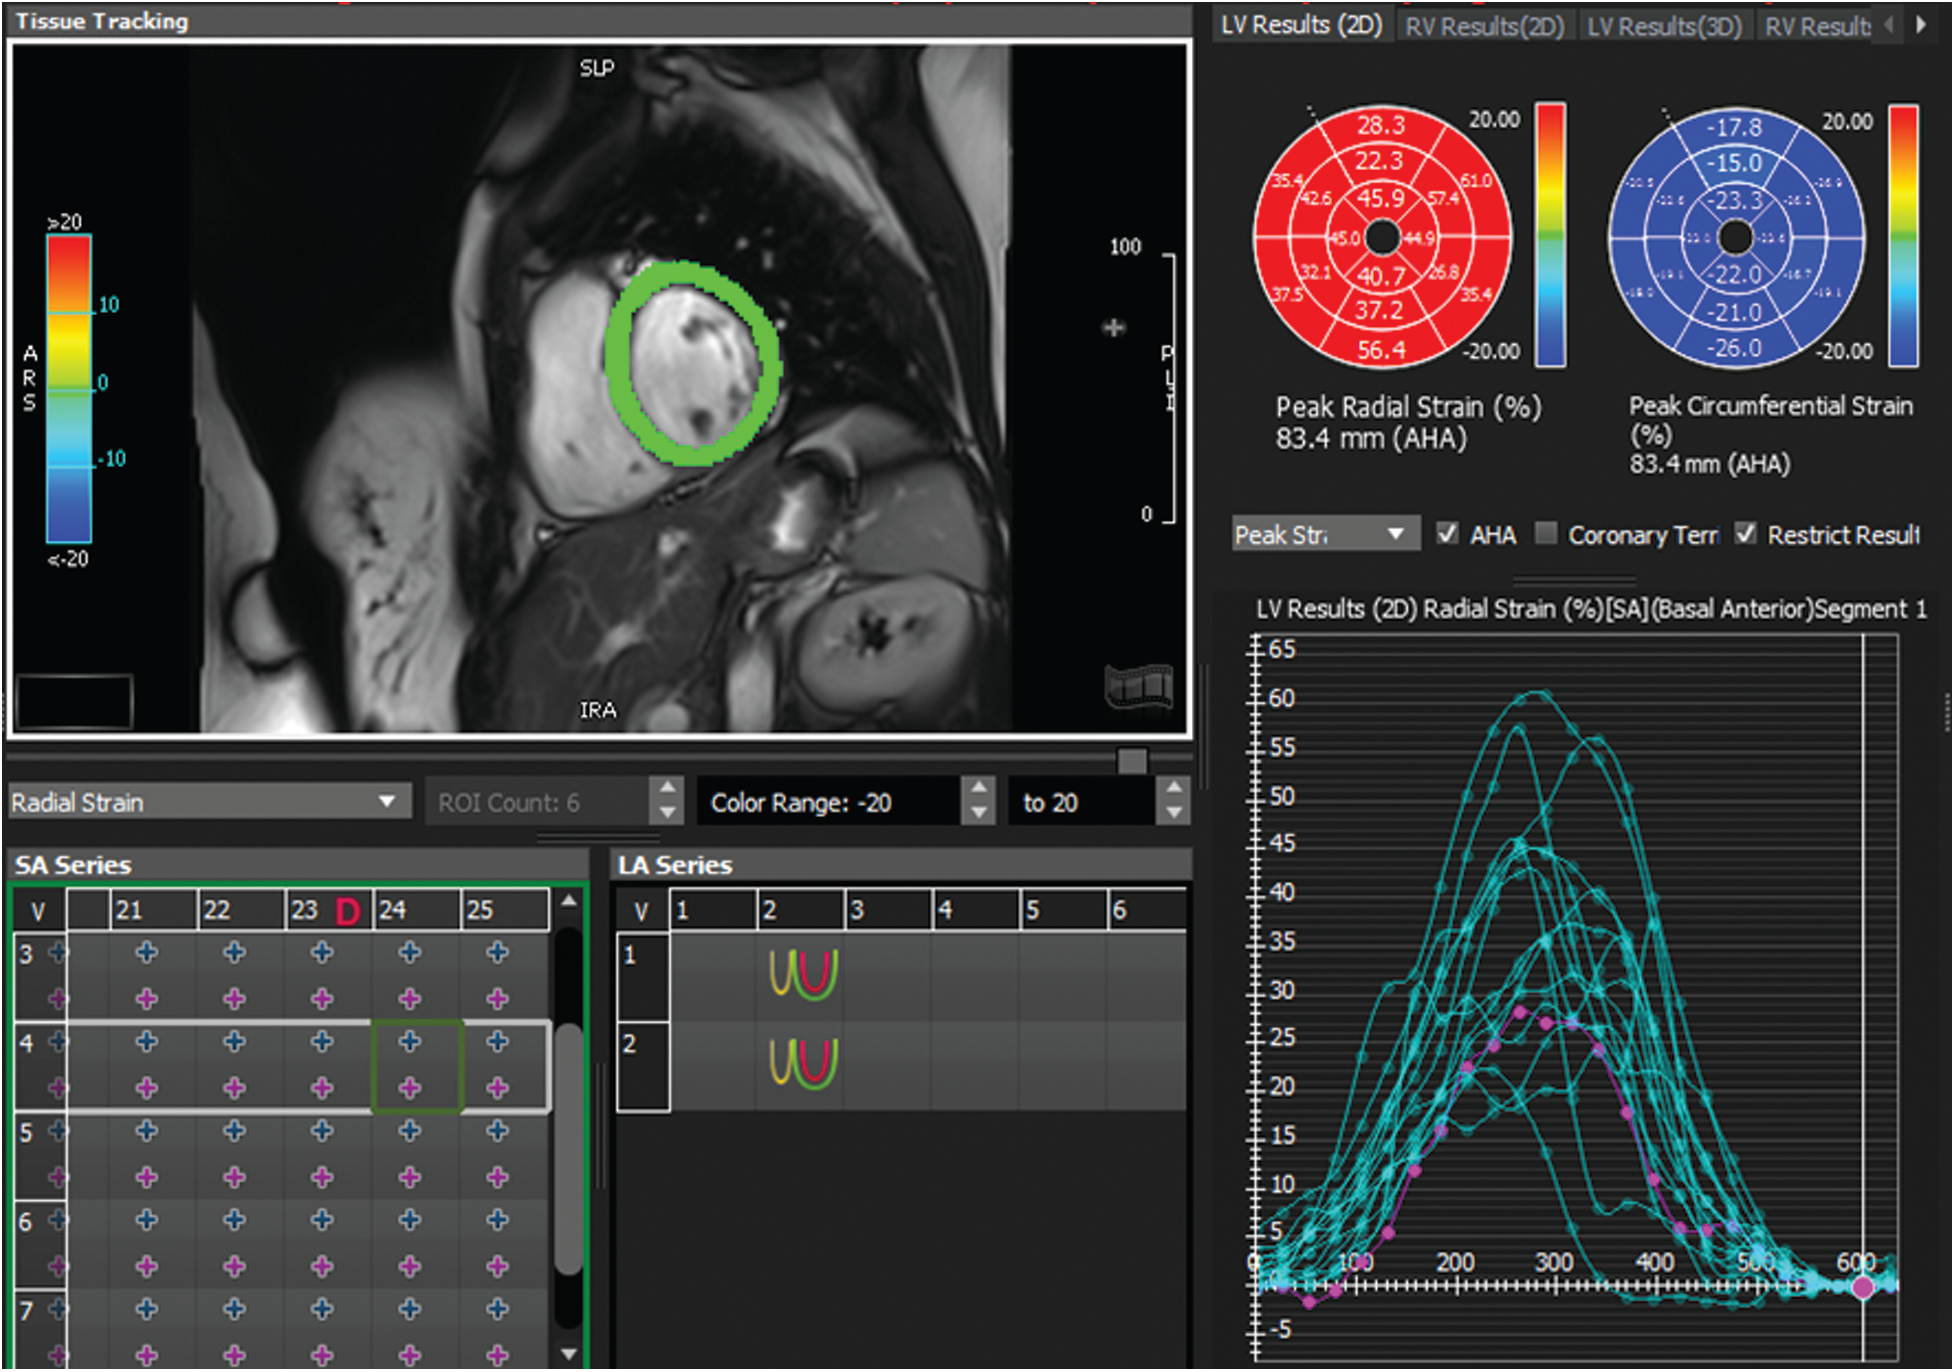

To validate our comparative study, we used the following protocol: for each patient, three parametric amplitude images were computed using three different approaches: covariance analysis, parametric images using Hilbert transform and those based on the monogenic signal. In this study, two experienced cardiologists using the 16 segments model recommended by American Heart Association/American college of cardiology (AHA/ACC) analyzed contraction abnormalities [31]. Following the 16 segments model, the myocardium is divided to six segments for respectively basal and Medio-basal slices and 4 segment for the basal slice. The 17 segments was not analyzed in CMRI short-axis view. Additionally, FT-strain analysis was performed offline for the same patients using dedicated software (cvi42, Circle Cardiovascular Imaging, Calgary, Canada). For each patient, segmental radial strain maps were computed according to the 16-segments model and the results of this analysis was used for the classification of different segments (see Fig. 4). The identification of myocardial dysfunction was based on three criteria: the motion of each myocardial segment, the myocardial thickness variation and the FT-strain results. According to the cardiologists ‘interpretation, each myocardial segment were classified as normal or with dysfunction. All the 640 segments (40 cine MRI sequences * 16 segments) were scored independently by the two cardiologists and the final interpretation results between them were served as a gold standard for the comparative study.

Figure 4: Example of radial strain map and time-strain curve derived from feature tracking software (Circle cvi42) for a patient with normal wall motion